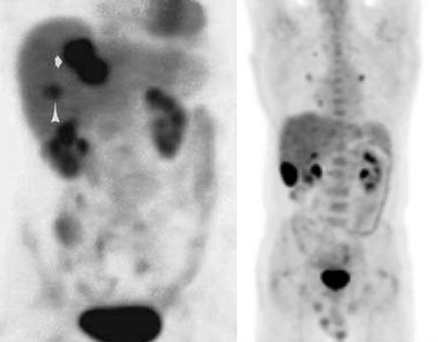

Image radiologique TDM et image de PET/CT des

adenocarcinomae du colon en extension localise et extension

metastasique :